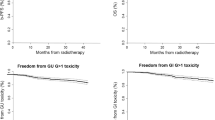

The time course of GI toxicity is shown in Fig. 1. No grade 4 toxicities were observed and 4 patients in total developed late grade 3 (1.2%) GI toxicity cumulated over 5‑year follow-up: 3 patients developed late rectal bleeding (mean 22.0 ± 15 months after radiotherapy, 10.0 ± 3.5 months duration) and 1 patient developed late fecal incontinence (48 months after radiotherapy, chronic); 1 patient with late rectal bleedings additionally suffered from proctitis grade 3. The maximum of acute GI toxicity occurred 6 weeks after the start of radiotherapy and decreased fast thereafter. Late grade 2 GI toxicity peaked at the 60-month follow-up and normalized thereafter. Overall, acute GI toxicity grade ≥2 was observed in 13.0% of patients and cumulative 5‑year late GI toxicity grade ≥2 in 12.1% of all patients.

The time course of GU toxicity is presented in Fig. 2. No grade 4 toxicities were observed. After 5 years of follow-up, 14 patients (4.0%) developed late grade 3 GU toxicity: 5 patients developed late grade 3 macroscopic hematuria (mean 25.2 ± 14.9 months after radiotherapy, 12.0 ± 0.0 months duration; two chronic cases); 8 patients suffered from late grade 3 urinary incontinence (mean 31.5 ± 13.9 months after radiotherapy, 20.0 ± 15.0 months duration; two chronic cases); 1 patient developed late grade 3 non-infective cystitis (36 months after radiotherapy, chronic). The maximum of acute GU toxicity occurred 6 weeks after the start of radiotherapy and decreased significantly within 6 weeks. GU toxicity was increased in patients with pelvic node irradiation: cumulative 5‑year late grade ≥2 GU toxicity was observed in 23.5% of patients in the group of prostate only radiotherapy and 34.1% of the patients with prostate and pelvic lymph node irradiation (p = 0.036, one-sided Fisher’s exact test). Late grade 2 to 3 toxicity showed a peak at the 36-month follow-up and decreased after the 60-month follow-up. Overall acute GU toxicity grade ≥2 was observed in 30.1% and cumulative 5‑year late GU toxicity grade ≥2 in 26.3% of all patients.